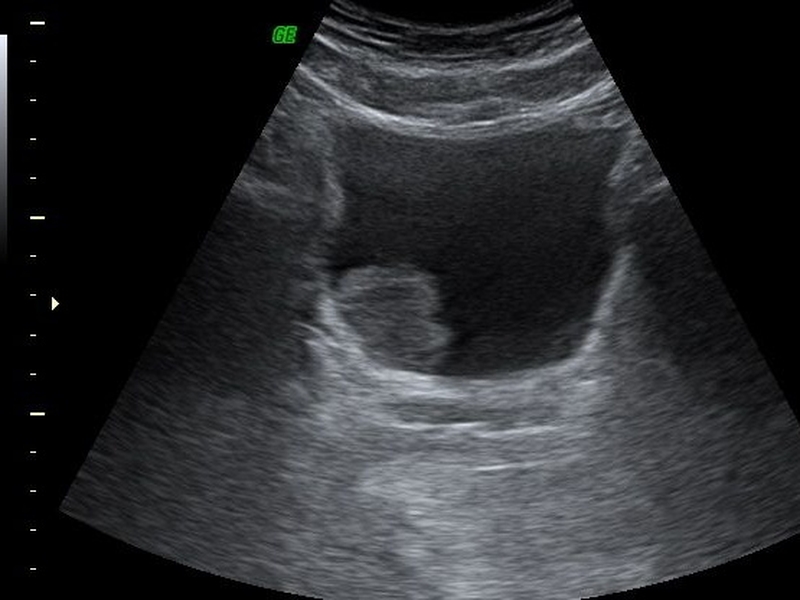

Siêu âm bàng quang là kỹ thuật sử dụng các sóng siêu âm có tần số cao để tái tạo lại hình ảnh của bàng quang. Hình ảnh kết quả của kỹ thuật siêu âm bàng quang sẽ thể hiện một cách tương đối chính xác và sắc nét cấu trúc bên trong của bàng quang cũng như lượng nước tiểu có trong bàng quang.

Siêu âm bàng quang hỗ trợ chẩn đoán bệnh lý nào? 3 Hình ảnh siêu âm bàng quang